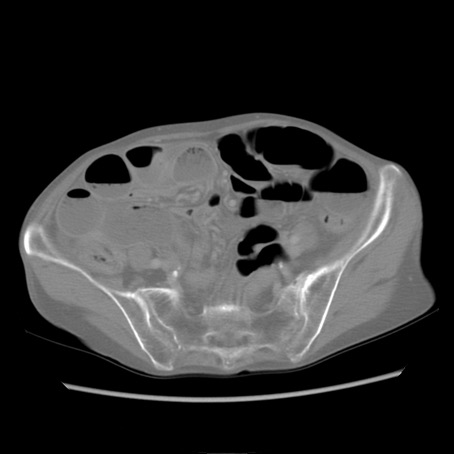

症例25(横断像)

【症例】80歳代女性

【主訴】胸のつかえ感

【現病歴】約9時間前に食後から胸のつかえた感じあり、嘔吐あり、来院。

【既往歴】胃癌(全摘)、胆摘、虫垂炎

【身体所見】心窩部に圧痛あり、反跳痛なし。

【データ】WBC 5700、CRP 0.05